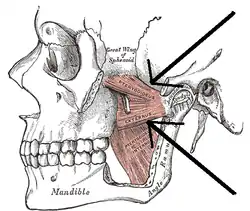

The Pterygoidei; the zygomatic arch and a portion of the ramus of the mandible have been removed (labeled as "pterygoideus externus", visible in pink at center) | |

The upper/superior head originates on the infratemporal surface and infratemporal crest of the greater wing of the sphenoid bone and inserts onto the articular disc and fibrous capsule of the temporomandibular joint.

The lower/inferior head originates on the lateral surface of the lateral pterygoid plate and inserts onto the neck of condyloid process of the mandible; upper/superior head